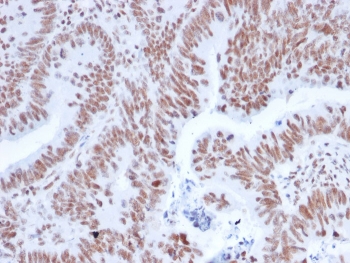

IHC staining of FFPE human colon carcinoma with NRF1 antibody. HIER: boil tissue sections in pH 9 10mM Tris with 1mM EDTA for 20 min and allow to cool before testing.